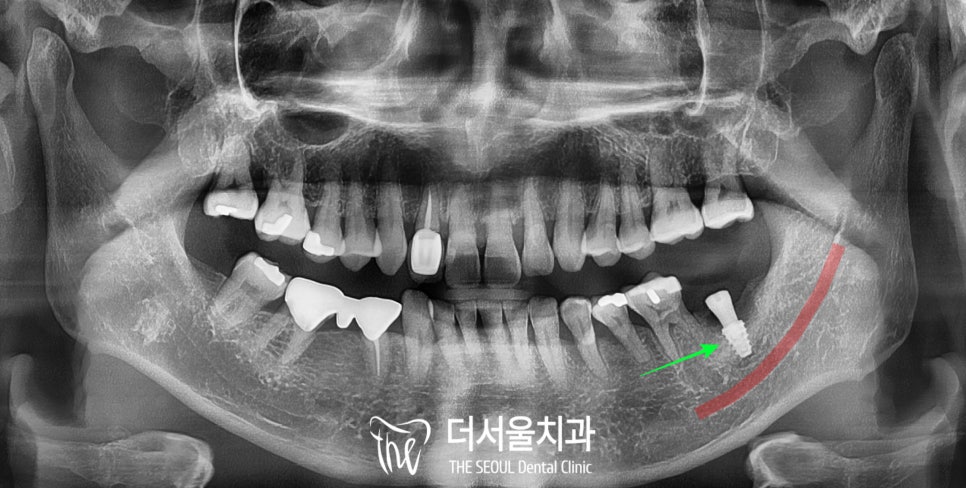

4. 디지털 임플란트 수술

모란역 치과 에서 환자의 동의하에

픽스처 식립을 모두 마치고 난

모습인데요,

잇몸뼈가 많이 녹아서

픽스처를 심는 것이 쉽지는 않았으나

그 주변으로 인공뼈 이식까지

성공적으로 진행해 드렸습니다.

또한 하치조 신경까지

거리도 충분히 확보하여

안전하게 심어드렸죠.

5. 크라운 연결

모란역 치과 에서는

이렇게 골질이 좋지 않고

잇몸 질환이 있는 경우,

치조골과 픽스처가

유착되기를 조금 더 기다립니다.

픽스처가 얼마나 단단하게

잘 고정되느냐가

구치부 저작기능 회복에 제일 주된

요소 중 하나이기 때문이죠.

4개월 정도 충분히 기다려준 뒤

임플란트 보철까지

모두 올린 모습입니다.

다행히 나사선을 따라

신생골도 잘 차올랐고

크라운도 잘 연결해드렸습니다.